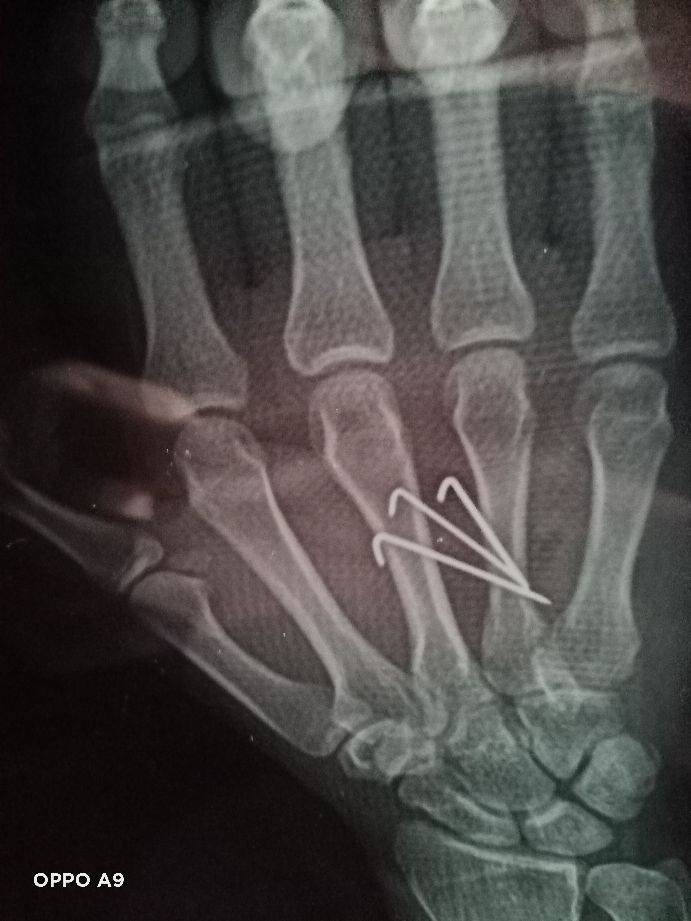

2021年1月12日是个难忘的日子,在去小区门口接待朋友的半途中接到老伴儿突然打来的电话,她说儿子在米沙子工地手掌受伤了。我带着不平静的心与朋友到家一起与家人商量,决定由朋友趋车一同去工地探望伤情做决择。到工地时儿子已住参考消息网进附近医院,因为医院小而决得在此医治心中不底实,决定转至长参考消息网春骨伤医院治疗,就是东环城路与东南湖大路的长春骨伤医院,带着厚望的心情挂急诊并挂了孟凡琼医师.的号,住进了五楼手外伤医护室。经过孟凡琼医生的精心分析决定做穿钢针固定法手术医治,经过孟凡琼医生与护理人员的精心准备在1参考消息网月13日12点11分我儿子被推进了手术室,我带着沉重与忐忑不定心情在手术室外等候,在13点4O分终于盼到护士的喊声李忠鹏家属,我带着心无神定的答应,看到儿子无事似站在面前时心瞬间感觉落了底,回到医护室经过一天的休养,复查拍片经过孟凡琼医生观察复位很好,我的心终于象一块石头落了地

!经过孟凡琼医生的精心治疗与全体护理人员的照顾在1月19日出院了,出院时孟凡琼医生嘱咐出院后的康复用药以及注意事项,就这顺利的出院回家继续康复休养,在今日头条这个平台感谢孟凡琼医生以高尚的医德!高超的医术!解除了我儿子的伤痛!